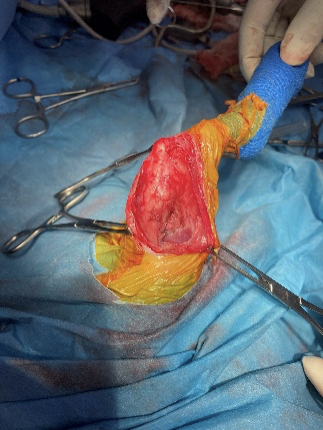

滑車溝造溝術

膝蓋骨の安定性を得るために、滑車溝を造溝した所です。滑車溝を削り取ってしまうだけの造溝の場合、骨の構造が硝子軟骨から線維軟骨に置き換わり治癒することはなくなってしまいますので当院ではトンネル法という本来の滑車部分を傷付けず、内部を掘り上から本来の滑車部分を落とし込むことで溝を深くする術式を採用しています。こちらの術式の場合削り取るだけの術式より手技は難しくなりますがより自然に近い形で滑車を残すことができます。

これにより膝蓋骨が滑車から脱線しにくくなります。